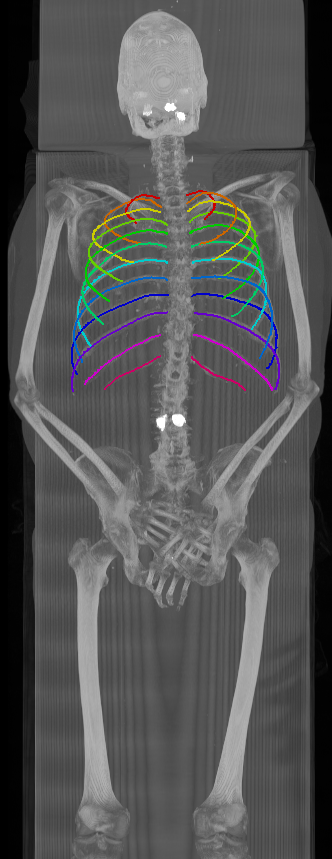

As can be seen from Table 2, we obtain overall good performance for the overall rib detection captured for example with an mean Dice of 0.84. Let us remark that for thin objects, such as the dilated rib centerlines, the Dice score constitutes a rather sensitive measure. The results indicate that detecting the first and twelfth rib pairs is more difficult for our network. While extraction of the first rib is more challenging due to, e.g., higher noise in the upper thorax or other bony structures in close vicinity (clavicle, shoulder blades, vertebrae), the twelfth rib can be extremely short and is easily confused by the neighboring ribs. For further illustration, Figure 4 shows the results on selected representative cases. Generally, the ribs are well detected without major false responses in other structures - despite all the different challenges present in the data. The color coding highlighting of the multi-label detection reveals that first and twelfth are mostly correctly detected. In few cases the network wrongly generated strong responses of the classes first rib or last rib for voxels belonging to the second or eleventh rib pair.

Refer to caption

Figure 4: Maximum intensity projections (MIP) of selected CT volumes overlaid with the multi-label output of the neural network (green: first rib; red: intermediate rib; blue: twelfth rib). The selected case above display common difficulties which are inherent in the data set, such as pads (a) or cables (b), internal devices such as pacemakers (c), stents (d), spinal (e) and femural/humeral implants (f), injected contrast agents (g), patient shape variations such as scoliosis (h), limited field of views (FOVs), i.e. partly missing first (i) or twelfth rib (j).